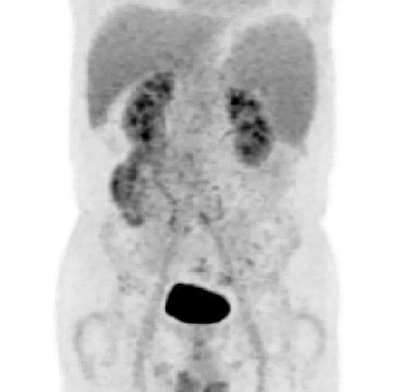

正电子发射计算机断层显像(PET-CT, 图1):1.脾脏增大伴FDG摄取增高,符合淋巴瘤PET-CT表现; 2.左肺癌术后,未见明显复发/转移PET-CT征象。

图1.患者脾切除术前PET-CT结果